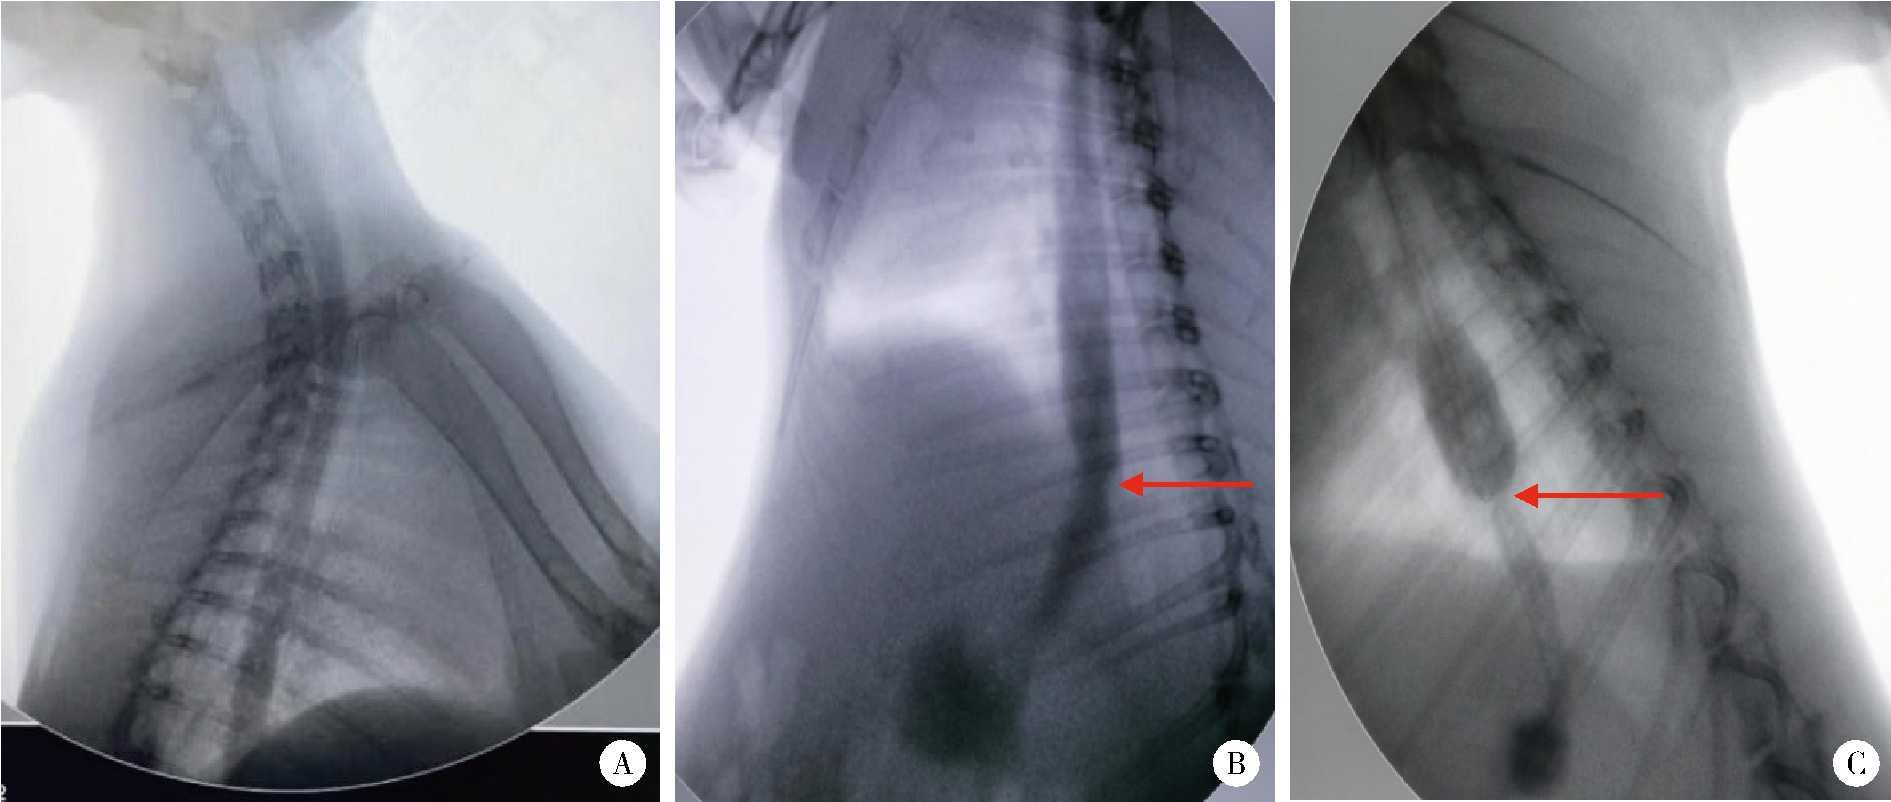

Figure 1

Comparison of intraoperative and postoperative esophageal endoscopic images in each group"

Figure 2

Esophagography at 4 weeks after operation in each group A, blank control group; B, experimental group Ⅰ; C, experimental group Ⅱ. The arrows show the sites of esophageal stenosis."